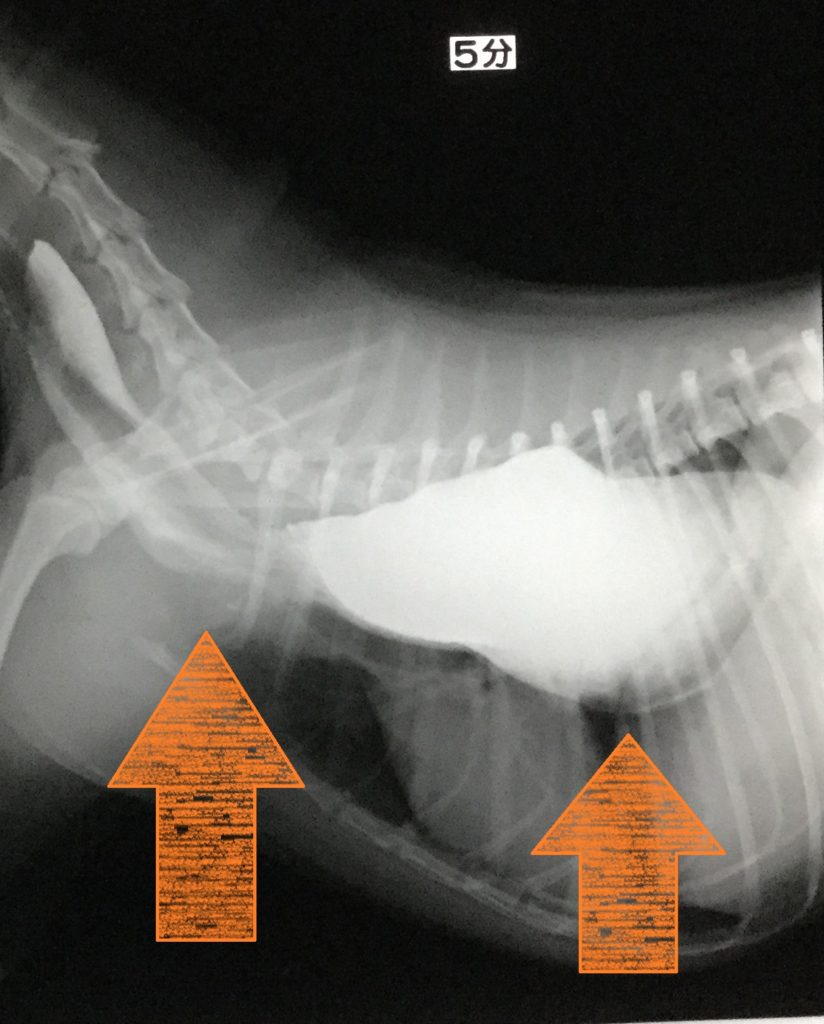

犬の巨大食道症、誤嚥性肺炎どうぶつ病院京都 四条堀川京都市。

食道拡張 巨大食道症 ♢消化器疾患♢院長ブログ。

巨大食道症尼崎の動物病院アニマルプラス。

巨大食道症診療コラム南が丘動物通信南が丘動物病院 兵庫県三田市の動物病院。

犬の巨大食道症草村動物病院 「動物の診察室から」。

巨大食道症宇賀ペットクリニック。